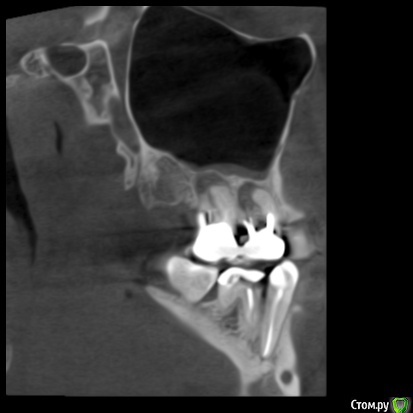

zubovolok Опубликовано 5 октября, 2018 Поделиться Опубликовано 5 октября, 2018 Коллеги подскажите пожалуйста как поступить в данной ситуации, после удаления 1.7и 1.6, чтобы кость восстановилась в хоть каком то объёме в идеале, чтобы избежать синуса? Ссылка на комментарий

zubovolok Опубликовано 5 октября, 2018 Автор Поделиться Опубликовано 5 октября, 2018 Как два сапога - пара.А сейчас какая высота кости?сейчас 10мм Ссылка на комментарий

zubovolok Опубликовано 31 июля, 2019 Автор Поделиться Опубликовано 31 июля, 2019 Подниму тему.вот Удалил 9 месяцев назад после удаления ничего не закладывал, только сгусток. Установил два импланта 1.7- 3.8 на 8 и 1.5-3.4 на 8, имплантиум. Но торк очень трудно получил , очень мягкая кость ( 4-ый тип), коллеги, как получить прогнозируемый, высокий, торк при таком типе кости? Ссылка на комментарий